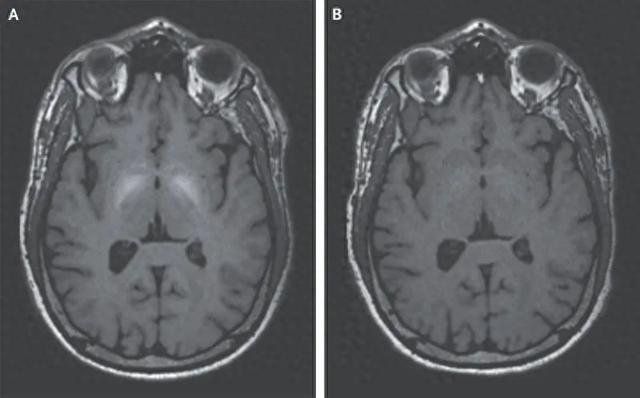

治疗经过:静脉EDTA治疗6个月 , 症状减轻 , 复查MRI病变消失(图B) 。